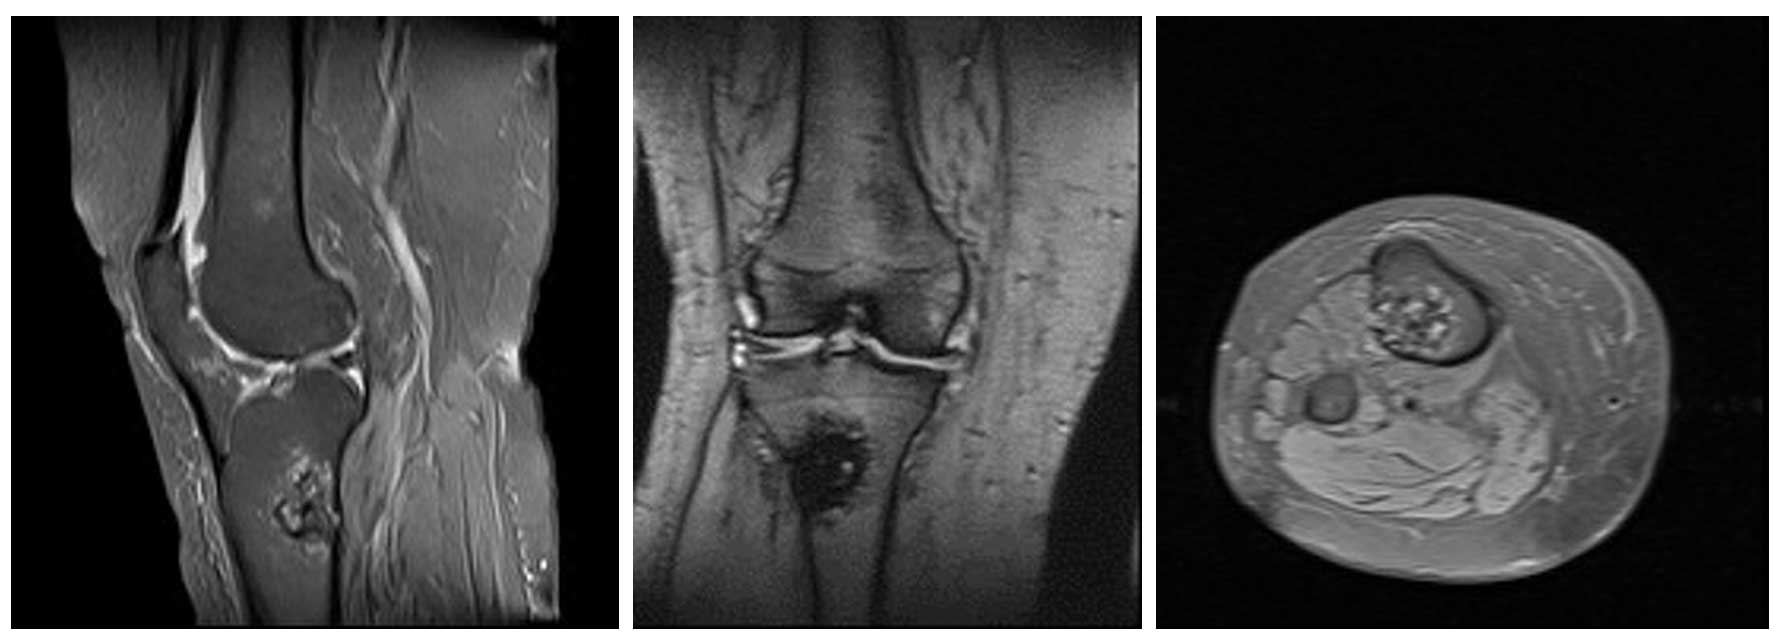

Ameliyat Öncesi: MR’da heterojen kitle çevresinde ödem ve korteks harabiyeti görülmekte.

Ameliyat Öncesi: Tomografide kıkırdak içerik ve kortekste düzensizlik görülmekte.